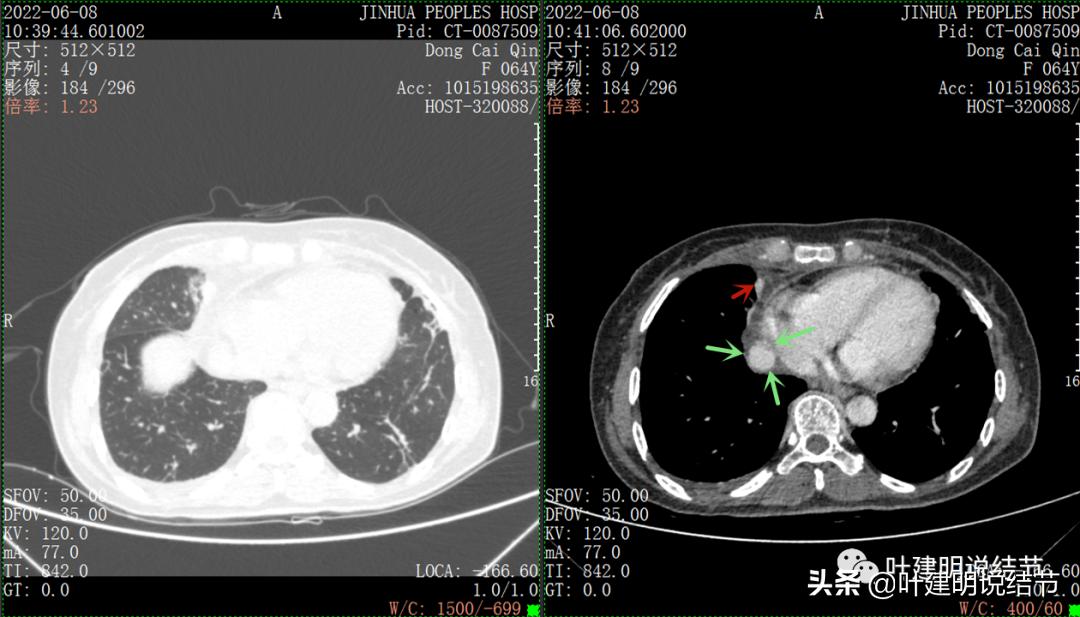

再来看看她的CT增强图像:

以下图片左侧是肺窗,右侧是纵隔窗。红色箭头示病灶,桔色箭头示无名静脉,黄色箭头示支气管,砖色箭头示上腔静脉,蓝色箭头示主动脉,紫色箭头示肺动脉。

无名静脉略受压

病灶纵隔胸膜侧非常光滑,说明来源于纵隔